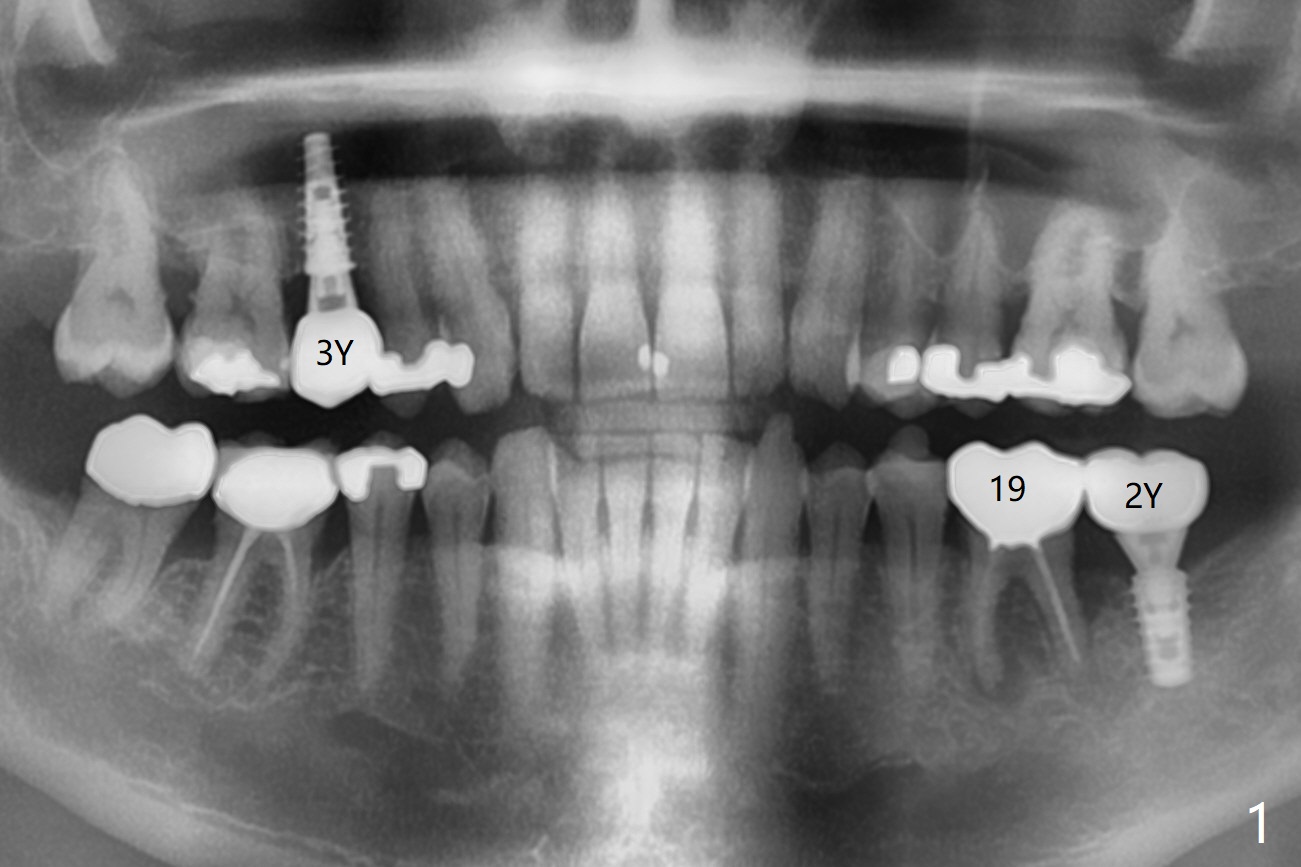

A 59-year-old man returns from endo-dontist office with diagnosis of "root fracture" of #19 (Fig.1).  The distal pockets are 5 mm deep with tender-ness, associated with bone loss (Fig.2 *).  Imme-diately post immediate implant placement, PRF or GEM21S mixed with cortical allograft will be used for bone regeneration.   Prior to bone graft, place an abutment, take a PA and make sure that the abutments at #18 and 19 are completely seated.  Reseat or trim the crestal bone if needed.   Prepare bleach gauze.  PRF will be used for sticky bone, which is more retentive than allograft hydrated with GEM21S.